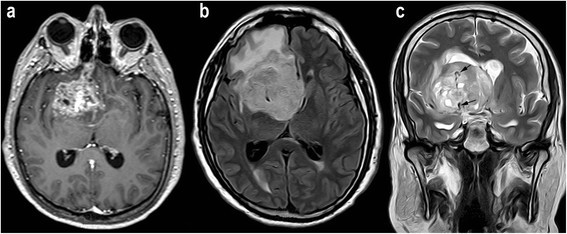

Figure 1

Example of MR images from a patient with glioblastoma (grade IV). a, Contrast-enhanced axial T1-weighted image shows an enhancing mass in the right frontal region. b, Axial FLAIR image shows peritumoral edema. c, Coronal turbo SE T2-weighted image revealing abnormal macroscopic vessels (arrows) within the tumor (neovascularization).